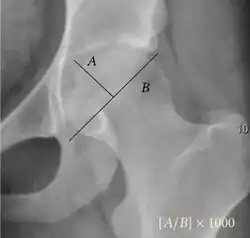

Reimer's migration index.

• Reimer's migration index (MI), also called the femoral extrusion index,[3] is calculated if hip dysplasia is detected. It can be used to indicate hip dislocation. It is the horizontal distance (parallel to the Hilgenreiner Line) between the Perkin line and the lateral border of the ossification center of the femoral head, divided by the horizontal width of the ossification center. The migration index is normally less than 33% by most sources,[9] but 25% and 30% has also been suggested.[10]